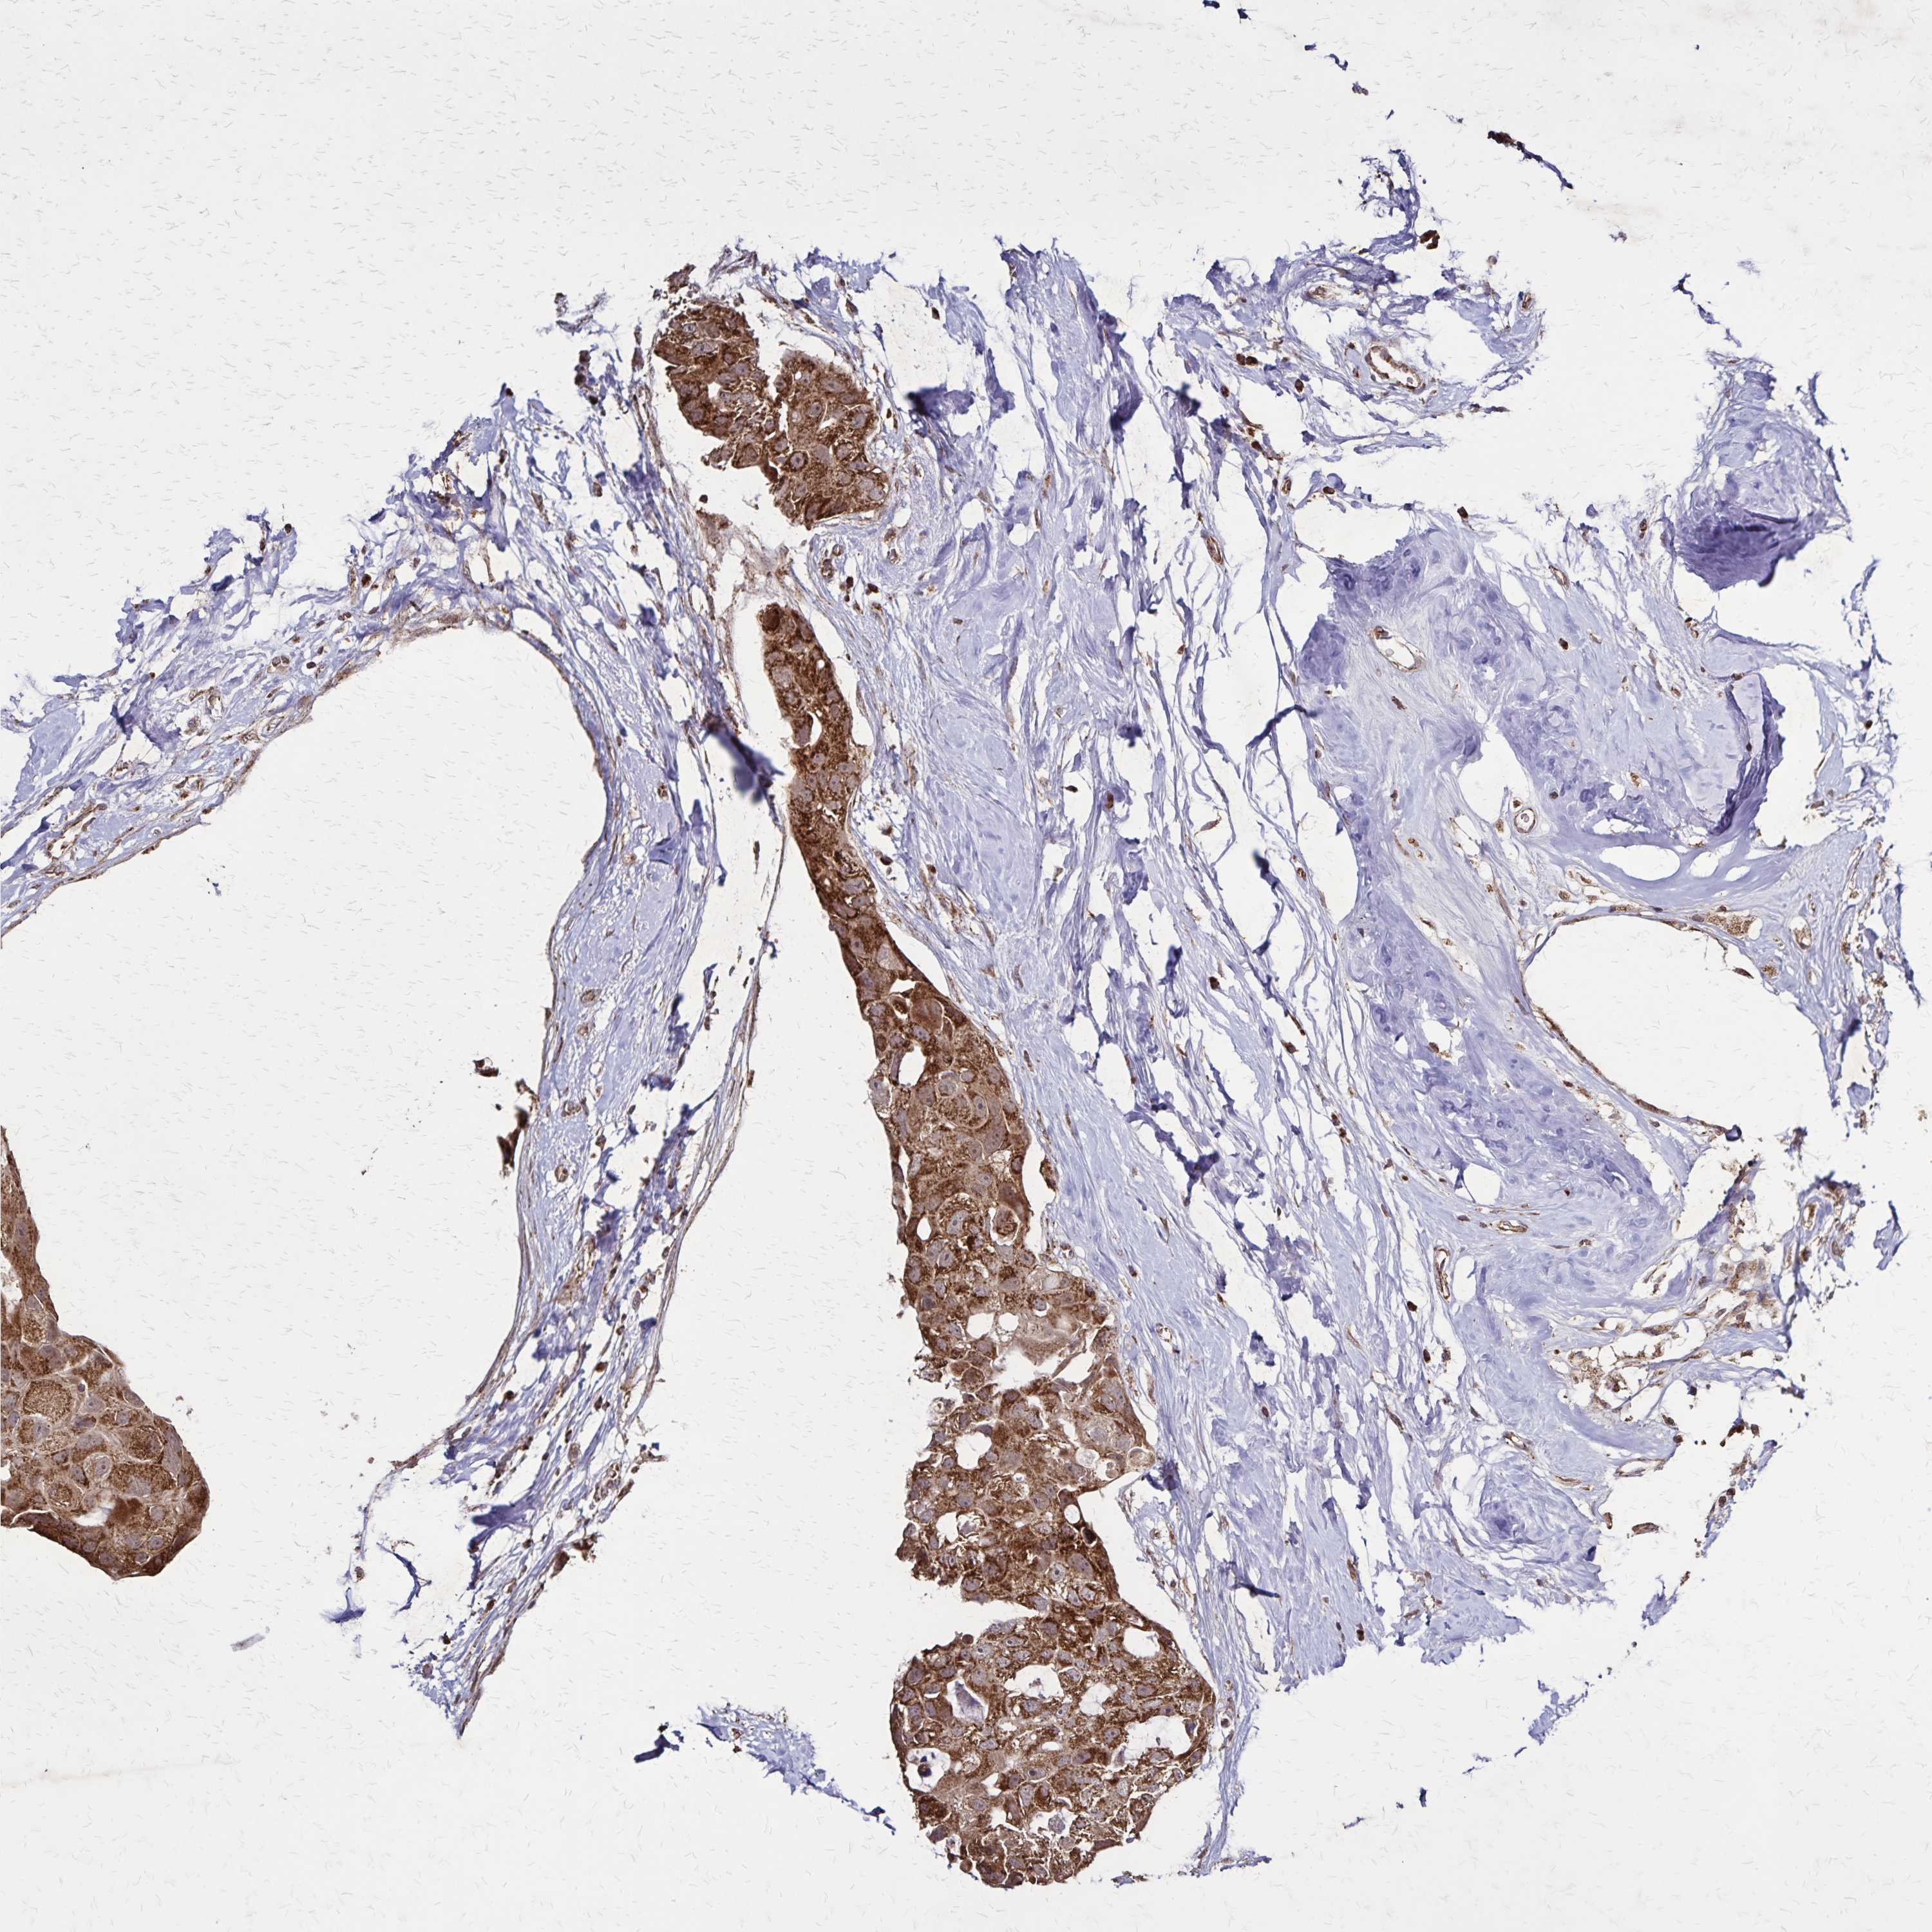

CANCER BREAST CANCER Show tissue menu

BRCA TCGA BRCA VALIDATION PROTEIN EXPRESSION

Breast cancer

Human cancer